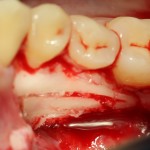

Однако, наши сверхкомплектные зубы вываливаться не хотят. Потому что их коронки образуют что-то вроде клина, который непросто вытащить через маленькое трепанационное отверстие.

Поэтому мы, всё также, с помощью ультразвука, отпиливаем коронку одного из зубов:

После чего, зубы вываливаются из лунок самостоятельно. В прямом смысле слова: